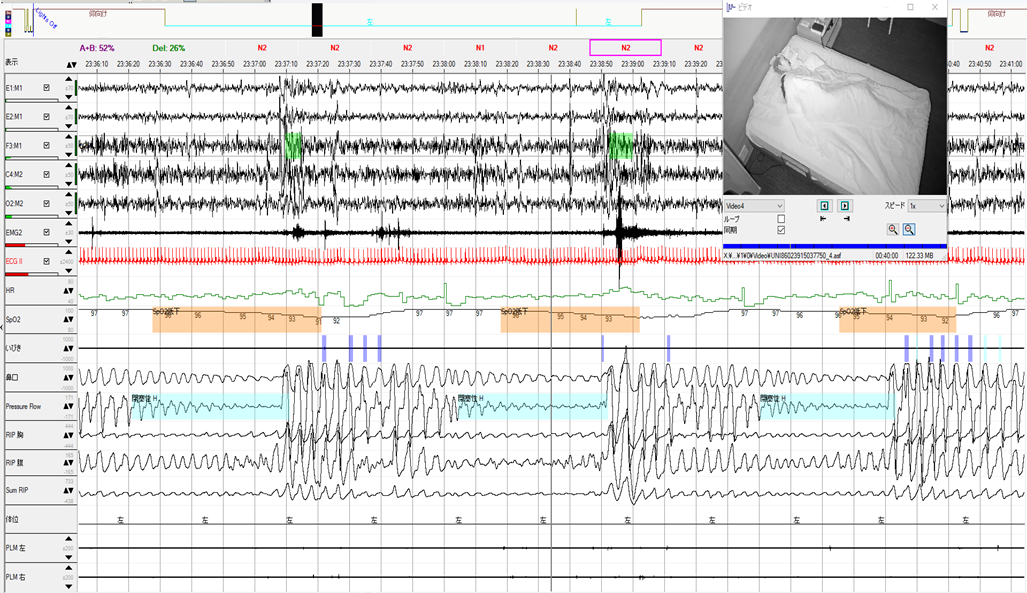

YUMINO'S コラム ゆみのPSGケースカンファ 学会・研究会 主要講演歴 著書出版歴 臨床研究 その他の活動 ゆみのPSGケースカンファ 2026年05月08日 記録前半は閉塞性呼吸イベントが主体で朝方CSR様の周期性呼吸を認めた症例 2026年05月01日 記録前半は閉塞性呼吸イベントが主体で朝方CSR様の周期性呼吸を認めた症例 2026年04月24日 超重症OSA症例の無呼吸と低呼吸 2026年04月14日 やせ型・若年者 でも重症のOSA症例 2026年04月10日 側臥位の就寝時間が長かったにも関わらず、重症の結果だったOSA症例 2026年04月03日 ノンレム睡眠側臥位の安定呼吸時の持続的なSpO2低下 2026年03月27日 CPAPタイトレーションで中枢性無呼吸が残存した症例 2026年03月13日 簡易検査結果と乖離して、大きく軽症化した症例 2026年03月06日 低振幅脳波で入眠判定が困難だったOSA症例 2026年02月27日 側臥位でも呼吸イベントが抑制されない重症OSAと徐波群発 1 2 3 4 5 年別 2026年 2025年 2024年 カテゴリー別